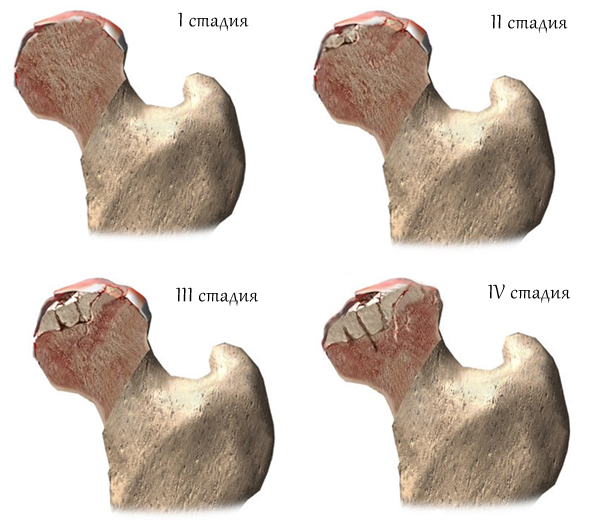

— асептический некроз головки бедренной кости;

В основе всех этих заболеваний лежит поражение хряща с последующим вовлечением в патологический процесс костной ткани.

На начальных стадиях всех вышеперечисленных заболеваний показано консервативное лечение, которое включает в себя медикаментозную терапию, физиотерапию, лечебную физкультуру, массаж и др.

На более поздних стадиях заболевания возможности ортопеда-травматолога ограничены только лишь хирургической помощью пациенту. В этих случаях операцией выбора является эндопротезирование тазобедренного сустава. Эндопротезирование, на сегодняшний день, является одной из наиболее эффективных операций в ортопедии, которая избавляет пациента от боли, восстанавливает движения в суставе, походку, конечность становится опорной и, что самое важное, улучшает качество жизни больного. Ежегодно в мире проводится порядка миллиона операций по эндопротезированию тазобедренного сустава.